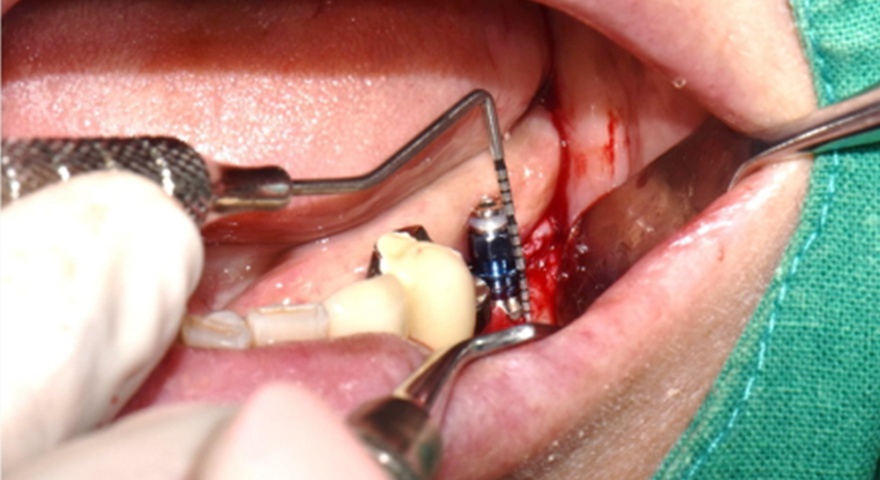

Після проведення стандартної імплантації в ділянках з оголеною різьбою було застосовано техніку DUK: на імплантат наносили спочатку пастоподібний матеріал, далі — гранули, після чого укладали мембрану та закривали клапті швами без натягу. Всі пацієнти отримували антибіотики (амоксицилін) та знеболення (ібупрофен), а через шість місяців — проходили контроль та біопсію ділянки.

Рис. 2. (A) Пацієнт із виявленою необмеженою (non-contained) втратою кісткової тканини та оголенням імплантату з букального боку на момент встановлення імплантату. (B) Нанесення основного шару пастоподібного кісткового матеріалу перед внесенням гранульованого кісткового трансплантата. (C) Укладання колагенової мембрани з покриттям зони трансплантації — від букального до піднебінного боку — та фіксували за допомогою внутрішніх періостальних швів. (D) Через шість місяців після аугментації — візуалізується регенерація кістки з букального боку в ділянці раніше оголеної різьби імплантату.